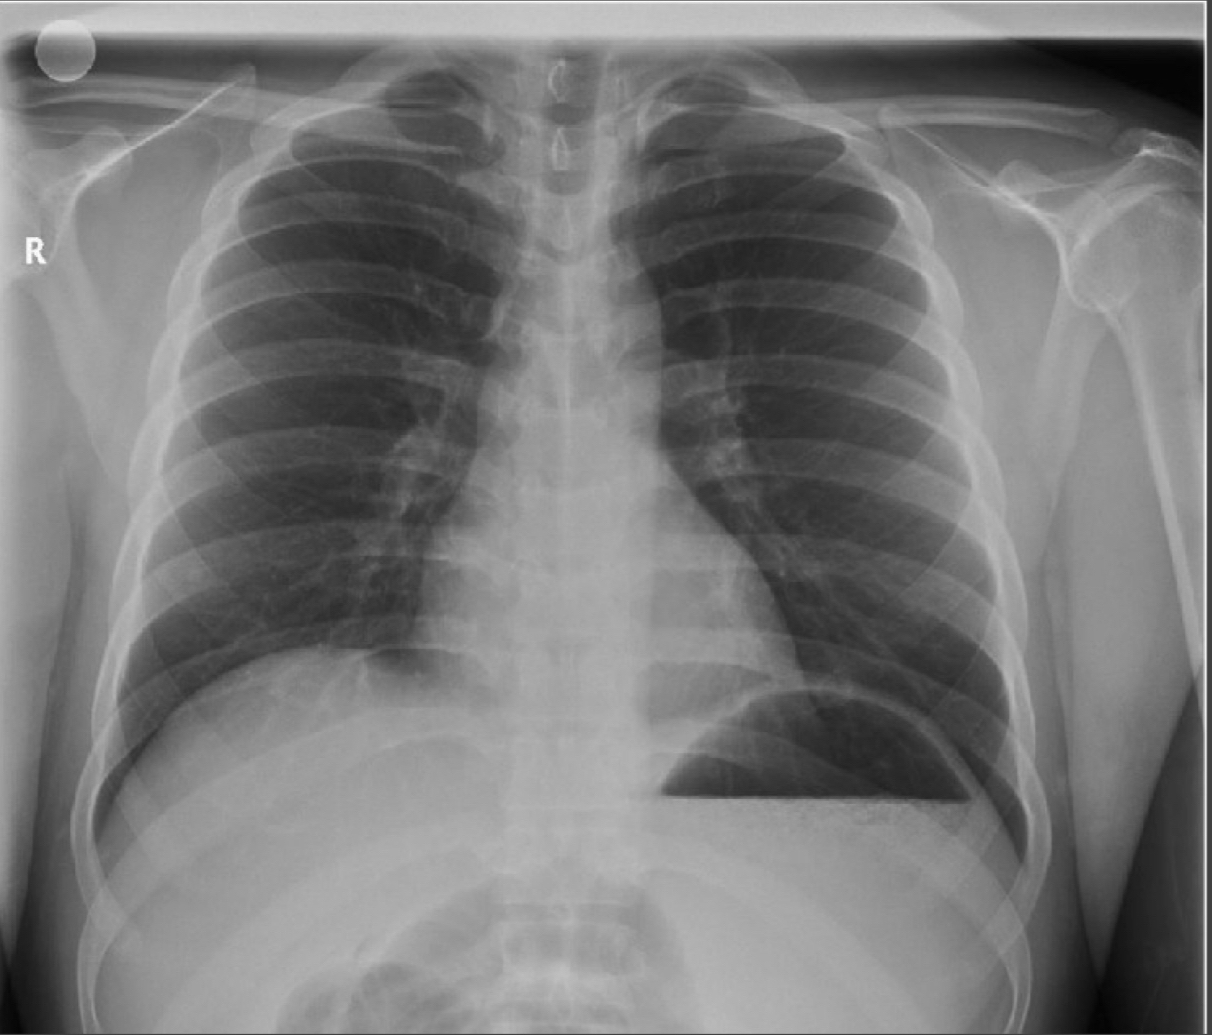

Views

PA (posterior-anterior): preferred; scapula do not obstruct lung fields.

AP (anterior-posterior): heart may appear larger.

Qualities to Assess

Rotation/Angle: twisted body or poor camera angle can distort heart size.

Inspiration:

Diaphragms should be at 9th rib on full inspiration.

Normal curve expected.

Flat diaphragms & expansion beyond 9th rib → air-trapping (asthma, COPD).

Exposure: must be adequate for clear structures.

Baseline Structures

Trachea, carina, right & left mainstem bronchi.

Lung fields, hilum, diaphragm.

Cardiac silhouette, pulmonary arteries, aortic knob.